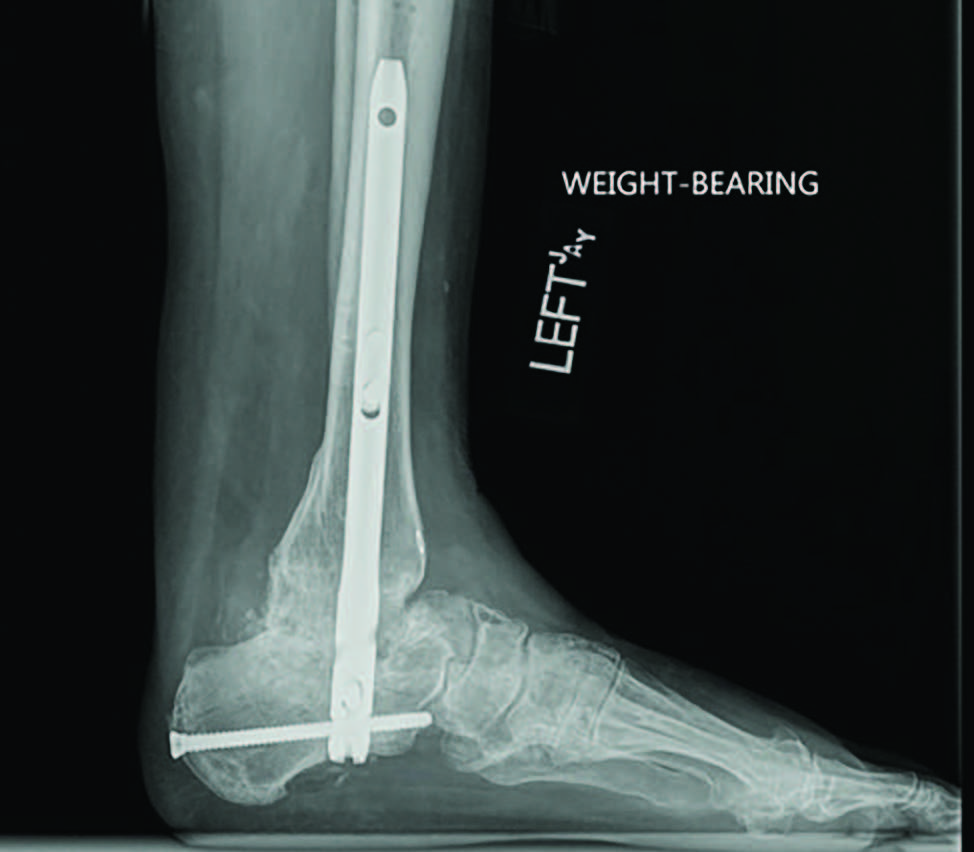

Radiographs demonstrated a subtalar joint dislocation with advanced degenerative changes (see first two images above). As we prepared for a subtalar joint fusion, we emphasized medical optimization of her vitamin D levels and made sure to rule out any metabolic weaknesses that would alter our techniques in the operating room. In my experience, it is best to perform these complex cases at facilities that can provide comprehensive patient care and possible admission if necessary.

For this patient, I ultimately performed a subtalar joint fusion with distal tibial autograft. She subsequently went on to develop a symptomatic non-union at six months postoperatively and collapse of her talus (see third image above). She again had medical optimization and we planned for a femoral head allograft reconstruction with Augment bone graft and intramedullary nail fixation. The patient went on to clinical success and there was demonstrated healing on a CT scan at four months post-op. She is now weightbearing in a shoe at two years post-op (see fourth and fifth images above).